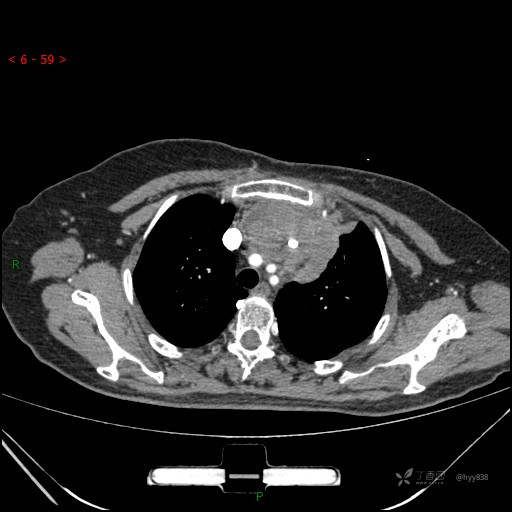

简要病史:患者诉3月余前患新冠肺炎,出现持续性胸闷,活动后可缓解,无胸前区压榨感,无畏寒发热不适,无胸痛咯血、呼吸困难,无恶心、呕吐,无腹痛、腹胀、腹泻等不适,未予以重视,未行特殊处理。患者胸闷持续存在,为进一步诊治,3天前于本院查胸部CT提示前纵膈团块状软组织密度影,肿瘤性病变可能,心包积液,左上肺磨玻璃结节,右下肺增殖灶可能建议进一步检查。门诊以“前纵膈占位” 收入我科。 患者本次起病来精神、食欲、睡眠尚可,大小便正常,体力、体重无明显变化。

辅助检查:CT

临床诊断:纵隔占位

动脉期